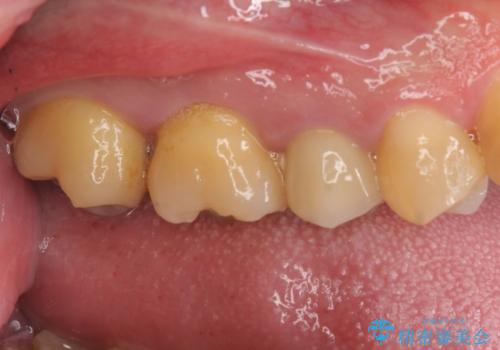

放置していた虫歯 セラミックインレーによる治療

- 食事の際に右上の奥歯が痛むので診てほしいとのことで来院。

視診では明らかに食べ物が詰まっているのがわかり、レントゲン写真では大きな虫歯の像が確認されました。

虫歯の大きさ次第でクラウンかインレーのどちらかになるだろうとご説明させていただき、今回はセラミックインレーでの治療となりました。